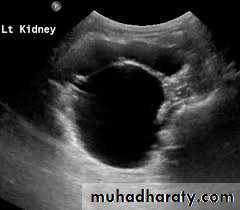

Ultrasonography; is the standard method for identifying hydronephrosis in infancy. Postnatal ultrasound imaging is usually deferred until day 3 of life, to allow for improvement in the relative oliguria, which could lead to underestimation of the degree of hydronephrosis.DIAGNOSIS

If prenatal US has shown a large or bilateral hydronephrosis, a follow-uprenal tract ultrasound scan should be performed soon after birth. If there

is a prenatal unilateral hydronephrosis (and the bladder is normal), the

scan is deferred until days 3–7 (to allow normal physiological diuresis to

occur, which may spontaneously improve or resolve hydronephrosis).